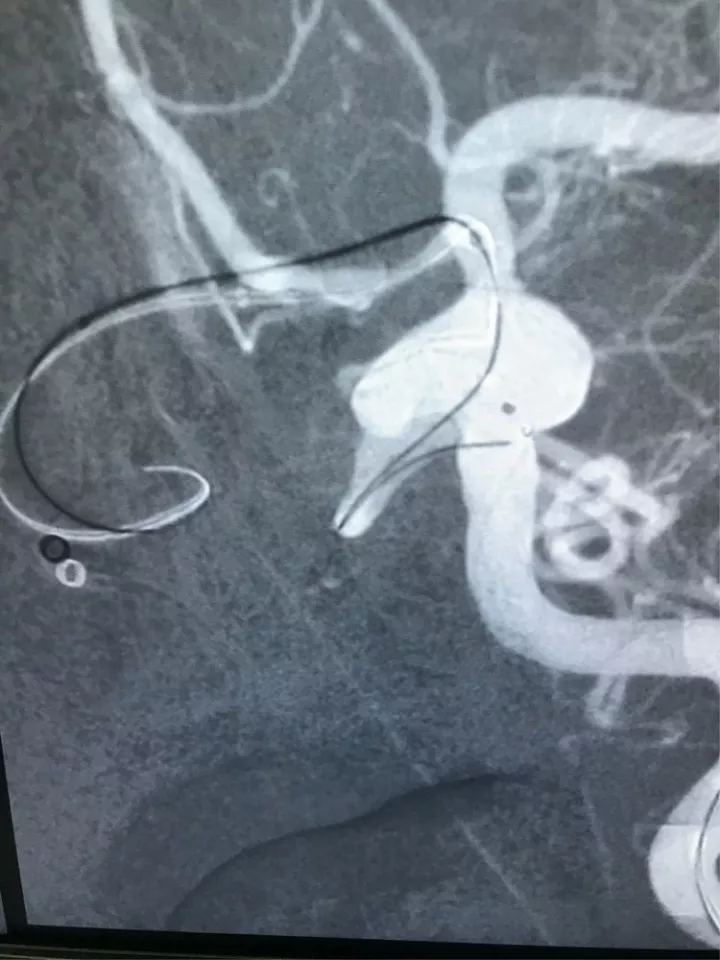

造影显示左侧后交通动脉瘤

椎动脉造影没发现大脑后动脉,双侧的大脑后动脉都是由颈内动脉-后交通动脉发出,双侧胚胎型大脑后动脉

我们来看看动脉瘤的结构:红色为颈内动脉走向,绿色为后交通动脉走向,蓝色为动脉瘤

栓塞的要点,既要致密填塞,又要保证颈内动脉和后交通动脉的通畅。决定通过对侧前交通动脉-颈内动脉远端-后交通动脉途径来置入输送支架的微导管,从后交通动脉释放支架直到颈内动脉末端,以达到一个支架对颈内动脉和后交通动脉的保护

双侧穿刺置鞘,对侧90cmCOOK长鞘+115cmNavien导引导管 ,导引导管头端尽量走得远一些

输送支架的微导管从右侧通过前交通动脉进入左侧

大脑前动脉与颈内动脉之间的夹角太小,导致微导管从大脑前动脉进入颈内动脉遭遇了一些困难

终于将导丝送入了后交通动脉以远

输送支架的微导管终于到位了,输送弹簧圈的微导管到位比较容易

释放支架